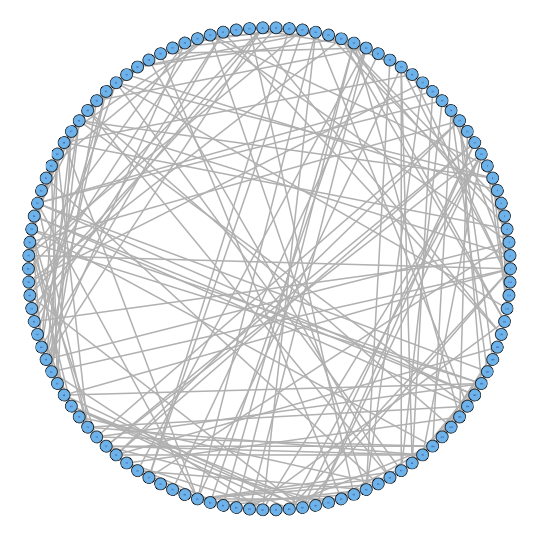

For our two-level problem (1.1.1), we must account for two sources of network variability when conducting population inference: (i) variability between subjects within a group and (ii) variability of the network selection procedure within a single subject. To see this, let us study a real multi-subject fMRI example. In Figure 2, we show estimated functional brain networks for subjects from the UCLA fMRI ABIDE data set INDI (2013). We describe the details of this data set, our pre-processing, and brain parcellation later in the Case Study in Section 5. In the top and middle panels, we estimate brain networks for each subject using graph selection methods for Gaussian graphical models (see Section 3.1 for details) and plot these as circle graphs to easily visualize network differences. It is clear that there are not only differences between autistic subjects and control subjects, but there is also large heterogeneity across subjects within each group. This is well-known in the neuroimaging literature (Milham et al., 2012; Nielsen et al., 2013), and makes finding statistically significant differences between subject groups much more challenging.

Less well studied in neuroimaging, is the second source of variability which arises from estimating networks for each subject instead of directly observing the networks. In the bottom panel of Figure 2, we re-estimate brain networks for a single control subject with bootstrap resampled data. It is clear that there is major intra-subject variability arising from our graph selection procedure. Indeed in neuroimaging, test–re-test studies which conduct brain imaging on the same subject in repeated sessions have shown high variability in the subject’s estimated brain networks (Wang et al., 2011). This also motivates the necessity of using a two-level model like (1.1.1) for population network inference as opposed to the one-level model and test statistics of the standard procedure.